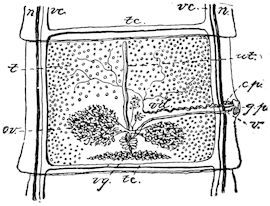

Fig. 1.—Rachitis in a young goat.

Fig. 1.—Rachitis in a young goat.